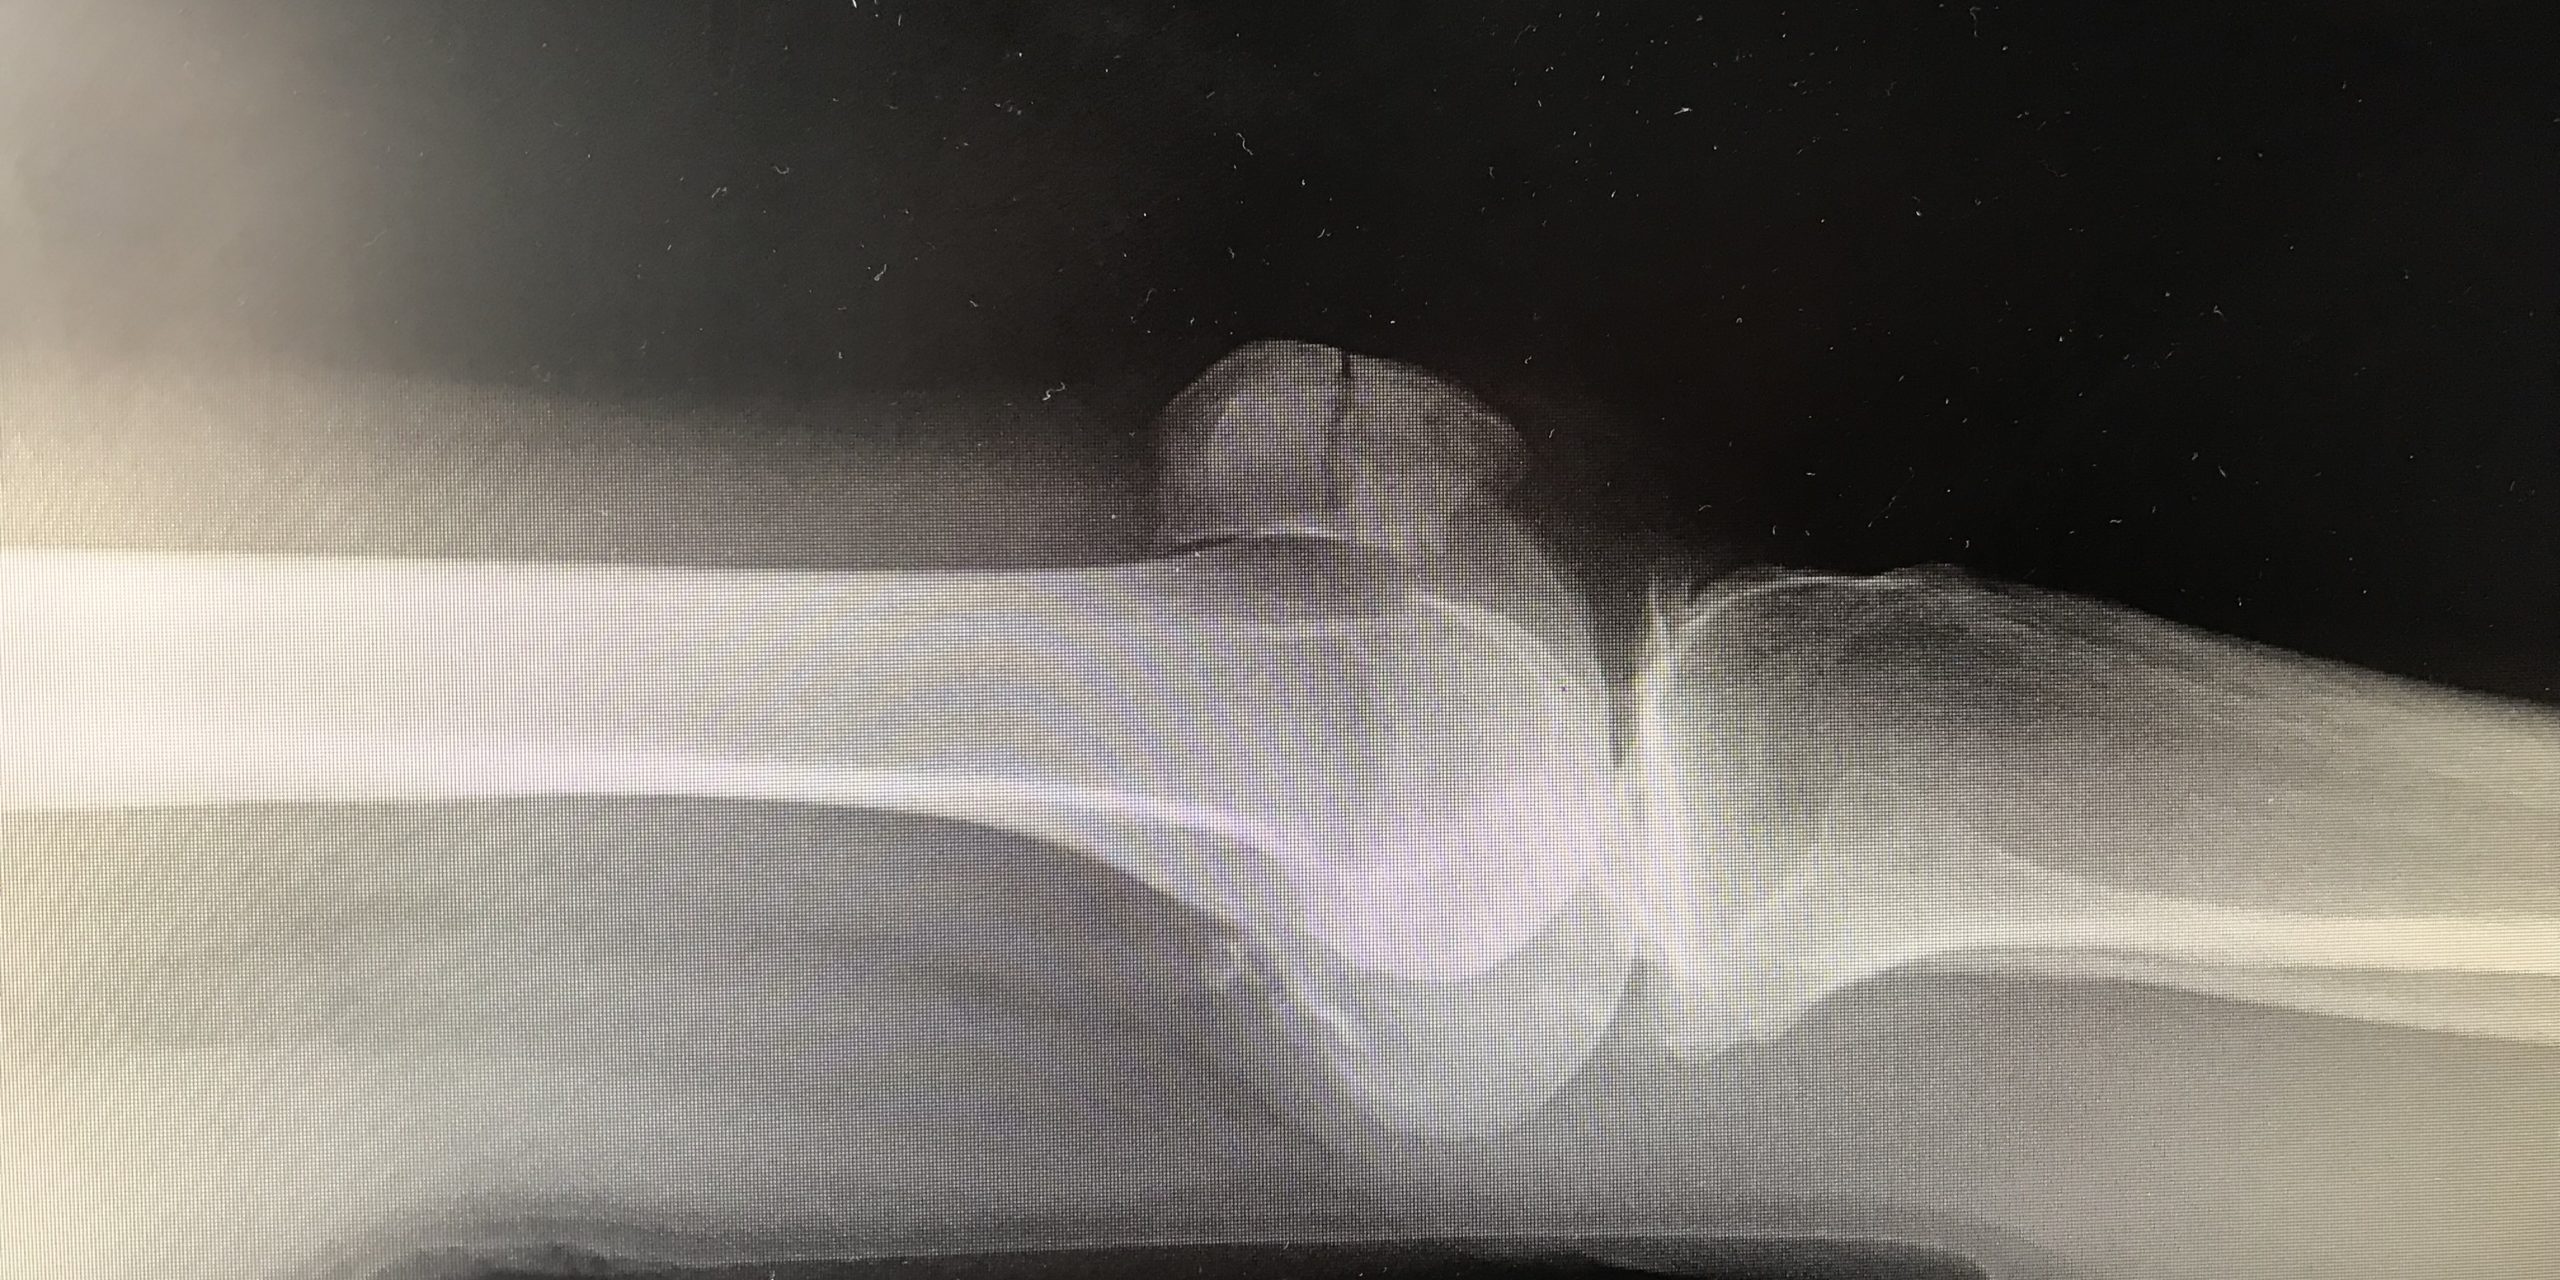

Joanna’s broken kneecap!

Worn out knees and then a broken kneecap on Boxing Day 2018 – yet with a Ski Mojo I skied (carefully) in mid-January without even a plaster cast.